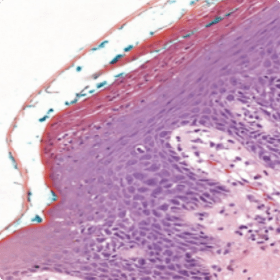

Dans les cas de psoriasis plus atypiques, une biopsie de la peau pourrait être utile10

des micropustules de Munro et Kogoj.

Micropustules de Munro et Kogoj